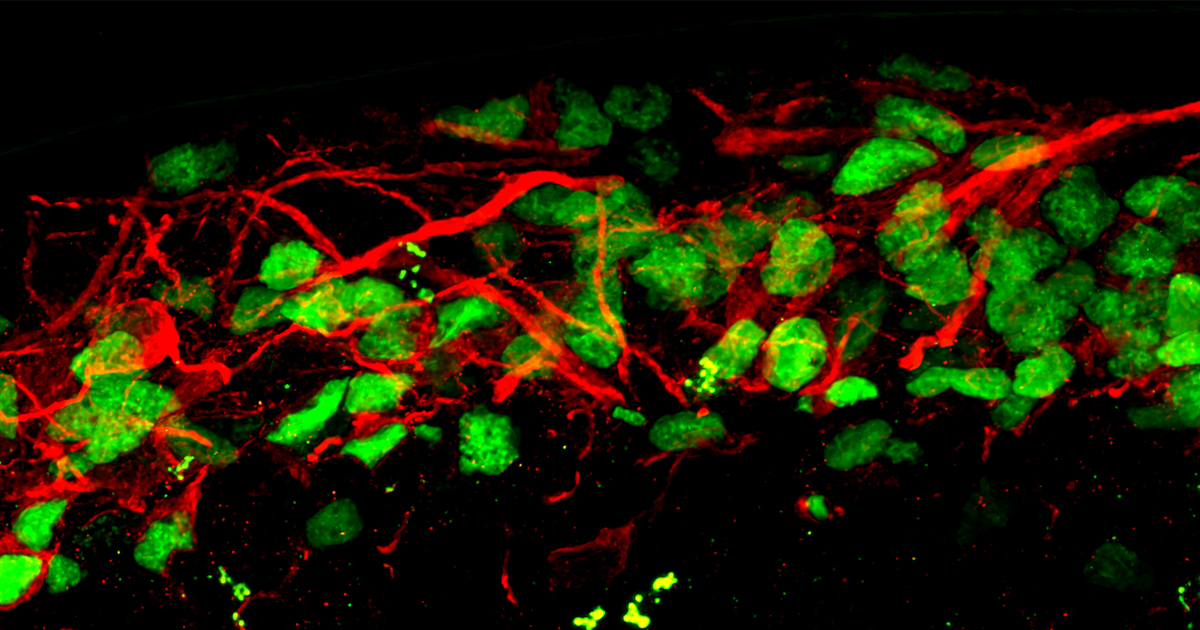

In this work, these lines were first differentiated to cortical neurons using 2D culture conditions and, as cortical hyperexcitability represents one of the hallmarks of FXS, the authors characterized the development of the glutamatergic and GABAergic systems through confocal analysis of immunofluorescence signals. For this purpose, in Brighi et al. a CrestOptics X-Light V3 spinning disk was used to acquire images to investigate the presence and the proper formation of glutamatergic and GABAergic synaptic components. Therefore, a side-by-side comparison of FMRP-WT and FMRP-KO cultures revealed that FMRP-KO neurons at day 54 displayed higher number of pre- (VGLUT1) and post- (PSD95) synaptic glutamatergic components demonstrating a temporary increase of excitatory glutamatergic synaptic markers during in vitro maturation (see Figure 3 and Figure 4 of Brighi et al. for the images and the method section “immunostaining and image acquisition and analysis of 2D cultures” for analysis details).

Further analyses on FMRP-KO 2D cultures have highlighted an altered neuronal and glial gene expression and proliferation, an increased network activity and a pronounced hyperexcitability, demonstrating how these 2D in vitro models are able

For 2D images acquisitions and analysis details see the method section “immunostaining and image acquisition and analysis of 2D cultures” of Brighi et al.